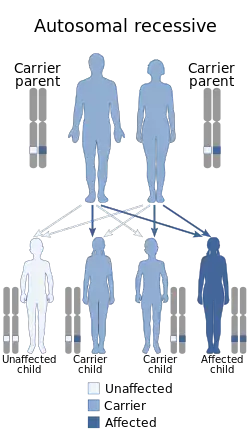

Urbach–Wiethe disease is a very rare recessive genetic disorder, with approximately 400 reported cases since its discovery.[1][2][3] It was first officially reported in 1929 by Erich Urbach and Camillo Wiethe,[4][5] although cases may be recognized dating back as early as 1908.[6][7][8]

Because Urbach–Wiethe disease is an autosomal recessive condition individuals can be carriers of the disease but show no symptoms. The disease is caused by loss-of-function mutations to chromosome 1 at 1q21, the extracellular matrix protein 1 (ECM1) gene.[12] The dermatological symptoms are caused by a buildup of a hyaline material in the dermis and the thickening of the basement membranes in the skin.[9] Urbach–Wiethe disease is typically diagnosed by its clinical dermatological manifestations, particularly the beaded papules on the eyelids. The discovery of the mutations within the ECM1 gene has allowed the use of genetic testing to confirm an initial clinical diagnosis. Periodic acid-Schiff (PAS) and immunohistochemical staining may also be used for diagnosis.[6][13]

Researchers have mapped Urbach–Wiethe disease to chromosome 1 at 1q21 and specifically identified the extracellular matrix protein 1 (ECM1) gene as the gene containing mutations that can lead to the development of the condition.[12] At this point, 41 different mutations within ECM1 have been reported to lead to Urbach–Wiethe disease.[13] These were all homozygous loss-of-function mutations (i.e. nonsense, frameshift or internal deletions).[9] It is an autosomal recessive condition,[2][13] requiring two mutated copies of the ECM1 gene to cause the disease.[20]

Urbach–Wiethe disease is very rare; there are fewer than 300 reported cases in medical literature.[2] Although Urbach–Wiethe disease can be found worldwide, almost a quarter of reported diagnoses are in South Africa.[2] Many of these are in patients of Dutch, German, and Khoisan ancestry.[2][12] This high frequency is thought to be due to the founder effect.[13] Due to its recessive genetic cause and the ability to be a carrier of the disease without symptoms, Urbach–Wiethe disease often runs in families. In some regions of South Africa, up to one in 12 individuals may be carriers of the disease.[9] Most of the case studies involving Urbach–Wiethe disease patients involve only one to three cases and these cases are often in the same family. Due to its low incidence, it is difficult to find a large enough number of cases to adequately study the disease.